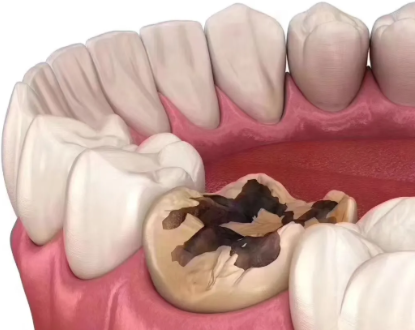

你是否正担忧龋齿不断腐蚀牙齿,却又不想立刻去治疗?别着急!本文为你带来5个实用技巧,帮助你在不治疗的情况下,让龋齿停止腐蚀。这些技巧涵盖日常口腔护理、饮食调整等方面,简单又有效。掌握这些方法,能让你更好地保护牙齿,提升口腔健康水平。接下来,就一起看看这些实用技巧吧!

当发现牙齿出现黑斑或有敏感症状时,一定要尽早就诊。特别多人觉得牙齿有点小问题不用管,殊不知,这可能会让龋坏越来越重度。如果龋坏进展至牙髓,那就会引发剧烈疼痛,到时候治疗起来不仅更麻烦,自己也要受更多的苦。所以,一旦发现牙齿有异常,就别犹豫,尽快去看医生,这样能避免问题恶化,让牙齿保持健康。